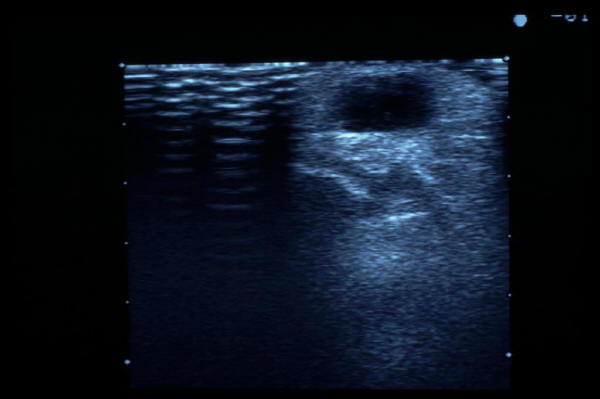

Quiste sinovial muñeca. Eco.

ECO cálculos en vías biliares

MO Colecistitis aguda.